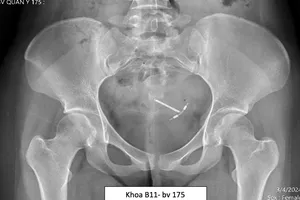

Có 2 vòng tránh thai trong bụng nhiều năm mà không biết

Hi hữu: Chiếc vòng tránh thai 'đi lạc' vào bàng quang

Phẫu thuật lấy vòng tránh thai lạc vào ổ bụng

Mổ nội soi lấy vòng tránh thai lạc vào ổ bụng

Vòng tránh thai xuyên tử cung vào ổ bụng